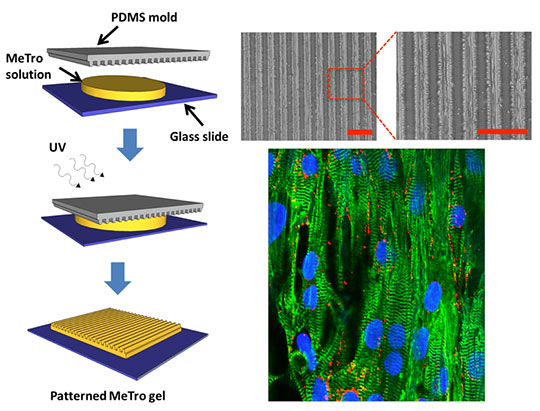

Эластичность сердечной ткани играет ключевую роль в надлежащем функционировании сердечной мышцы, например при сократительной активности. Поэтому, исследователи разработали новый вид гелей, с использованием растяжимого человеческого белка под названием тропоэластин. Исследователи подвергли тропоэластин ультрафиолетовому свету, и это сделало его значительно более упругим и сильным веществом.

Вверху справа: Удлинение клеток сердца и выравнивание их на поверхности

микроструктурированного гидрогеля MeTro.

Внизу справа: Структурированный гидрогель MeTro окрашен, чтобы показать выравнивание

клеток сердца на 8-й день. Зеленый и красный цвета - это критически

важные белки в клетках сердца, и синим показаны ядра клеток сердца.

Чтобы убедиться, что клетки формируют необходимую структуру, в лаборатории Хадемхоссейни ученые использую технологию 3D-печати и методы микротехники для создания структур в гелях. Благодаря этим структурам, клетки растут именно так, как необходимо исследователям. В результате этих экспериментов были созданы небольшие заплатки из клеток мышцы сердца, аккуратно выстроенных в ряд, синхронно сокращающихся в пределах канавок, сформированных в этих эластичных субтрактах. Эти микроструктурированные эластичные гидрогели могут быть однажды использованы в качестве заплаток для сердца.